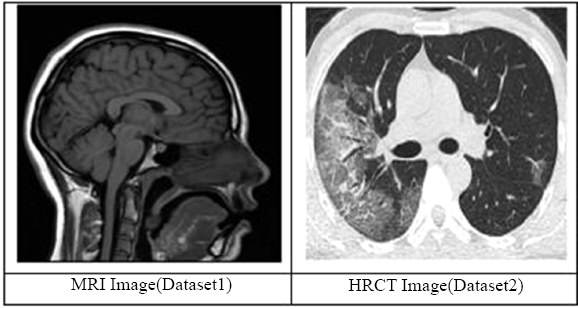

3.1.1. MR Image

Based on the image characteristics, the present scan is most likely to be identified as a T1-weighted MRI sequence. The T1-weighted image also shows that the gray substance of the brain is darker than the white substance, and the cerebrospinal fluid within the ventricle also appears dark. This sequence is mainly applied to high-resolution anatomical imaging to produce clear boundary demarcation between various structures of the brain and is well employed in the architectural variability of the human brain [62].

3.1.2. HRCT

According to the image characteristics, this scan is probably a High-Resolution Computed Tomography (HRCT) of the chest. In HRCT imaging, lung tissue is imaged in a thin slice thickness of 1-2 mm, which enables excellent depiction of lung structures and minimal parenchymal modifications. Its late phase is preferable for evaluating lung diseases, as it provides excellent resolution and contrast [62].

Fig. (3) demonstrates the dataset images. It shows two images, MRI and HRCT.

Fig. (3).

Dataset (MRI & HRCT image) [62].